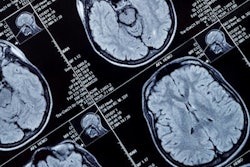

The research will investigate CDM in patients with mild cognitive impairment to evaluate for possible Alzheimer’s disease and other dementias. The companies aim to demonstrate the accuracy and efficacy of CDM compared with other diagnostic methods including standard MRI and PET.

Oxford Brain Diagnostics has developed a new software analysis tool that the company claims is more sensitive to neuronal degeneration in the brain’s gray matter, supporting earlier diagnosis of many forms of neurodegenerative diseases such as Alzheimer's disease, posterior cortical atrophy, and frontotemporal dementia. The tool is pending 510(k) clearance from the U.S. Food and Drug Administration (FDA).

Under terms of the deal, Oxford Brain Diagnostics will analyze data from patients and controls scanned at several SimonMed facilities, applying CDM, which tracks the diffusion properties of water in the brain’s gray matter. The idea is that disrupted diffusion can result from tissue degeneration and is an early indicator of several forms of dementia.